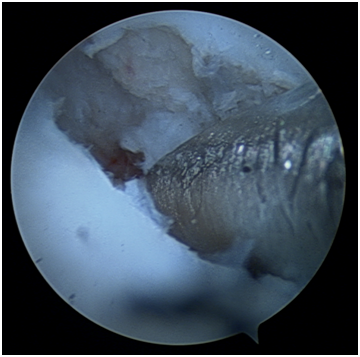

The arthroscopic procedure started with the realization of standard radio-carpic initial portals; medium-carpal portals helped with the identification of the pseudarthrosis focus (Figure 4). The pseudarthrosis focus was blown out (Figures 5 & 6). The spongious graft of the contralateral iliac crest was harvested. Placement of the graft through the midcarpal portal of visualization by adapting the arthroscopy trocar (Figures 7-9). The traction was withdrawn. The graft was fixated with a percutaneous anterior approach and arthroscopic support and placement of the double compression screw with radiographic support (Figure 10).

Figure 7 Arthroscopic placement of iliac crest graft with the help of the visualization trocar.

Figure 8 Bone Graft between the scaphoid pseudarthrosis.

Figure 9 Arthroscopic view of the graft.